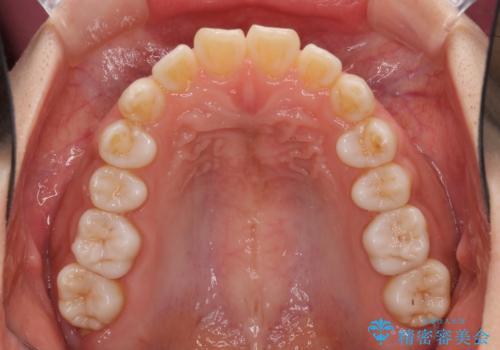

インビザラインによる軽度な出っ歯の矯正治療

- 上の前歯の出っ歯を治したいとのことで来院された患者様です。

上下顎ともにIPR(歯と歯の間を削る)と歯列全体の拡大によって口元が引っ込むように設計し、インビザラインにより治療を行うこととしました。

どこまで口元を引っ込めることができるのか、患者様自身も正直分からない部分があったため、少しずつ治療ゴールを変更しながら仕上げていきました。

気になっていた前歯の飛び出した印象は、最終的にはスッキリと引っ込み、大変満足していただきました。